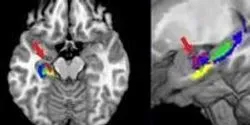

Innovation enables better visualization and interpretation of data from cell microscopy